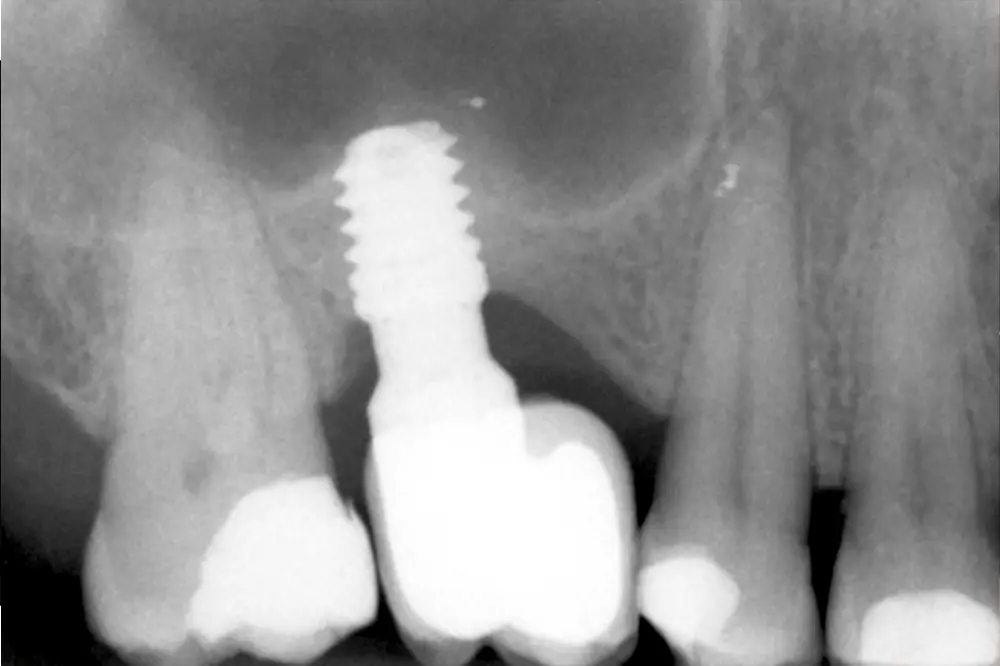

Llegados a este punto, se retira el implante de 4,5 mm al igual que en el caso anterior, de forma totalmente atraumática, y se coloca un implante de 6,5 mm de longitud (fig. 13). Se realiza la carga del implante a los 4 meses y tras 3 años de seguimiento comprobamos la estabilidad total del tratamiento realizado (fig. 14).

Fig. 14. Radiografía a los 6 años de la carga con la estabilidad total del tratamiento realizado.